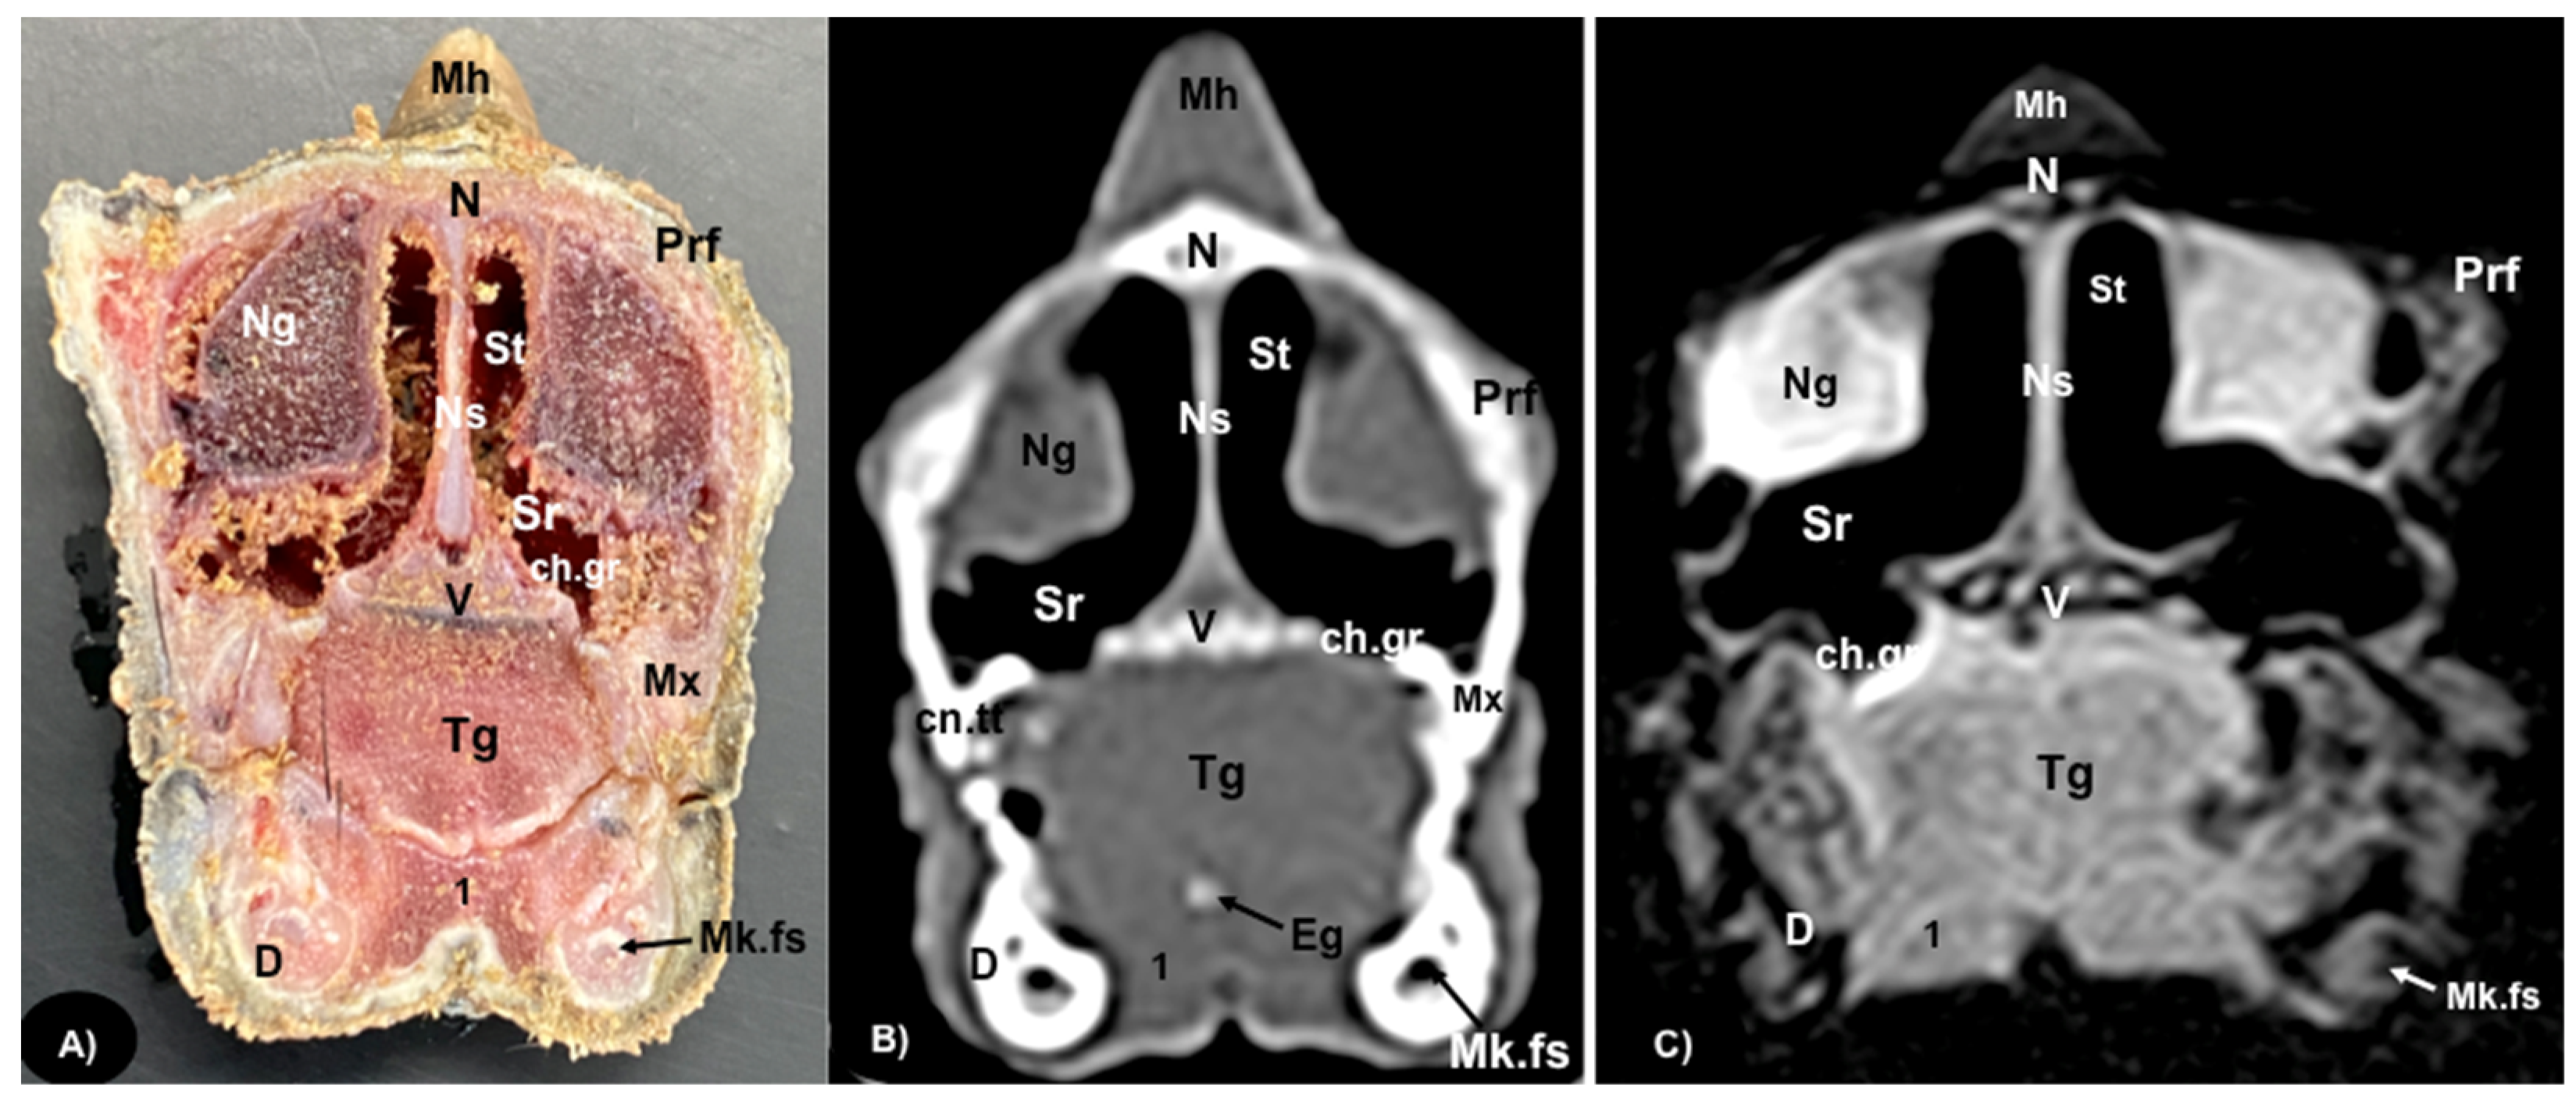

Figure 2.

Transversal gross-section (A), CT bone window (B), and MRI in T1W (C), images of the head of rhinoceros iguana at the level of the nasal cavity corresponding to line I in Figure 1. Mh: Medial horn. N: Nasal bone. Prf: Prefrontal bone. Ns: Nasal septum. Ng: Nasal glands. Sr: Subconchal recess. St: Stammteil. ch.gr: Choanal groove. V: Vomer. Mx: Maxillary bone. Tg: Tongue. Eg: Entoglossal process of the basihyal bone. cn.tt: Canine tooth. 1: Musculus geniohyoideus + Musculus hyoglossus + intermandibularis. D: Dentary bone. Mk.fs: Meckelian fossa.

3.1. Anatomical Sections

3.2. Computed Tomography (CT)

Concerning the nasal cavity, the transverse CT image showed the nasal glands as symmetrical bilateral structures, with regular and well-defined margins, located on both sides of the nasal cavity and with soft tissue attenuation (Figure 2B). Moreover, those structures with intraluminal gas content such as the nasal conchal recess (Figure 2B), oral cavity, nasopharyngeal duct, trachea, adductor fossa (Figure 4B) and the otic cavity (Figure 6B) were identified with this technique, appearing with a vacuum effect. In addition, there were areas of soft tissue attenuation medial to the mandible and bilateral to the hyoid apparatus, compatible with the intermandibularis, genihyioideus and hyoglossus muscles (1 in Figure 2B and Figure 3B), the pterygoideus, omohyoideus, sternohyoideus and ceratohyoideus muscles (2 in Figure 4B), the adductor mandibulae externus medialis and superficialis muscles located, respectively, dorsomedially and ventrolaterally to the adductor fossa (3 and 4 in Figure 4B and Figure 5B).

3.3. Magnetic Resonance Imaging (MRI)

The soft structures of the iguana’s head, such as the central nervous system as well as the eyeball’s structures (vitreous humor and lens), the oral cavity with the tongue and the masticatory muscles, showed an accurate visualization using MRI (Figure 2C, Figure 3C, Figure 4C, Figure 5C and Figure 6C). Therefore, an increased volume of both eyeballs in proportion to the size of the head was seen in all sequences (Figure 3C and Figure 7B). As in CT, the structures with gas content (Figure 2C and Figure 6C) appeared with a vacuum effect, being hypointense in all sequences. The nasal glands were bilaterally symmetric, with regular and well-defined margins, located on both sides of the nasal cavity, being iso/hyperintense in T1W and T2W sequences, compared to the encephalic grey matter (Figure 2C and Figure 4C). In contrast, the medial horn appeared hypo/isointense on T1W and T2W sequences concerning the white matter and with mild differentiation of the external bony cortex in relation to the white matter (Figure 2C).